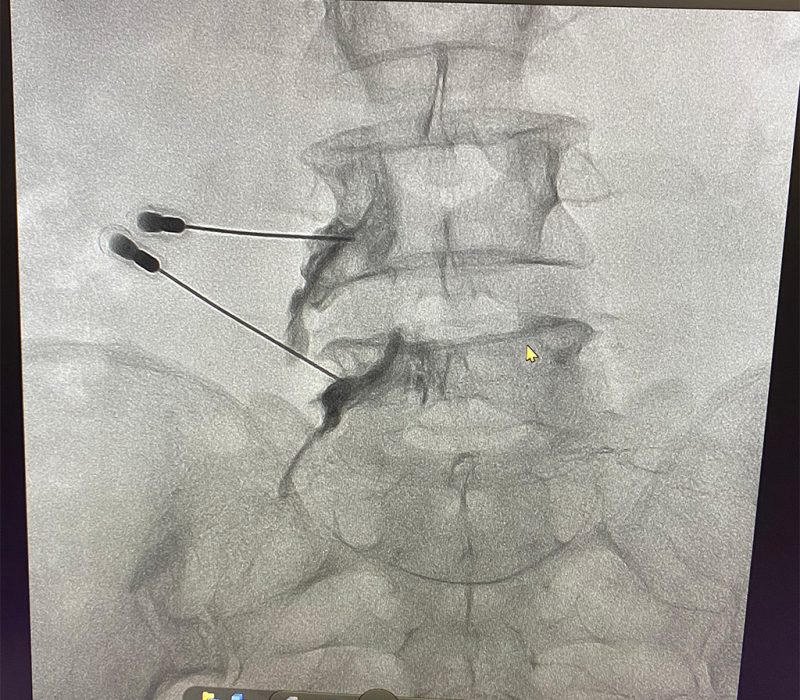

Un bloqueo es una inyección dirigida a un músculo, nervio o articulación de un anestésico local acompañado de un antinflamatorio, se basa en la interrupción de la nocicepción o de la señal dolorosa, en otras palabras se trata de «apagar» el dolor. Puede ser temporal y reversible por lo que en ocasiones le llamamos bloqueos diagnóstico, pues al aislar una estructura dolorosa podemos identificar de forma más específica el origen del dolor y posteriormente ofrecer técnicas con mayor durabilidad.

Estos procedimientos se deben realizar siempre bajo guía fluoroscópica y/o con guia de ultrasonido, esto permite obtener imágenes en tiempo real de las estructuras internas con lo que el procedimiento tiene mayores índices de eficacia al estar seguros que el medicamento esta siendo depositado en la estructura deseada y ofrece mayor seguridad para el paciente.